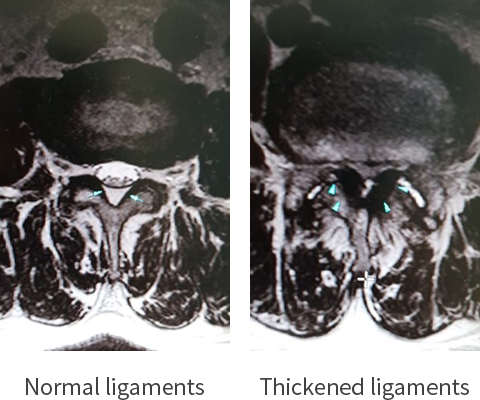

is caused by various diseases such as Sprain, Disc Bulging/Herniation, Foraminal Disc Herniation, Degenerative Disc Disease, Spinal Stenosis, Spondylolisthesis, Spondylolysis, Fracture, Facet Cyst, Tumor, Scoliosis, etc.